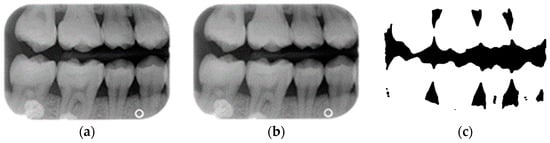

- Single-tooth extraction algorithm

A complete BW varies due to factors such as angle, exposure size, the number of teeth, and interproximal spacing. Using fixed parameters and thresholds can lead to misjudgments and low segmentation efficiency. To enhance flexibility and operability, the algorithm uses adaptive thresholds tailored to each BW based on brightness, size, and the number of teeth. Each BW is pre-processed before segmentation due to variations in mouth shape, tooth shape, and imaging angle. This study first applies to a gaussian high-pass filter to eliminate noise, reducing segmentation errors. Next, the images undergo binarization and erosion techniques to clarify background contours, making them easier to distinguish, as illustrated in Figure 3.

Figure 3.

BW image preprocessing. (a) Original BW. (b) Gaussian filter. (c) Horizontal erosion after binarization.

Due to angular issues in a BW, horizontal and vertical lines may not fully separate the teeth. This study addresses this by rotating and binarizing images multiple times to enhance the contrast between teeth and gaps. High-contrast images allow for accurate identification of tooth gaps through pixel horizontal projection as shown in Figure 4a. The image is divided horizontally into three parts, masking the upper and lower sections to focus on the middle, like the upper and lower sides of the red box in Figure 4b are masked. The valleys of the projection line in this region are identified as the x-minimum value, and the y-coordinate of the valley represents the vertical height separating the upper and lower rows of teeth after rotation. Additionally, during each rotation, a projection is made to identify the trough position in the middle of the image. The trough values (x-minimum) at each angle are compared to determining the optimal rotation angle for horizontal segmentation. Initially, the image is rotated within a range of plus or minus 15 degrees, in increments of 5 degrees. By comparing the trough values at each angle, the most suitable rotation angle for horizontal cutting is identified, as shown in Figure 4b.

Figure 4.

Horizontal projection of the rotated image. (a) BW rotated +5 degrees; (b) BW rotated +10 degrees.

According to Table 1. After performing small-angle rotations and comparing the trough values at each angle, it was determined that the lowest trough value (x = 36) occurs at a rotation of 11 degrees, which is lower than the trough value (x = 40) obtained at the initial rotation of 10 degrees. Therefore, it can be concluded that a positive 11 degrees is the most suitable rotation angle for this BW, which is more favorable for subsequent horizontal segmentation. If a smaller rotation angle is used from the beginning to find a suitable angle, multiple calculations will be required within the same range of angles. However, by gradually rotating the image in two steps, one large angle (5 degrees) and one small angle (1 degree) to obtain the most suitable rotation angle, we achieve the same result and find out the suitable angle more quickly. After rotating the image of each BW to a suitable angle, the height of the trough (y-value) is found. The height of the plumb coordinates of the troughs are found and the horizontal line separating the upper and lower jaws is plotted using the height of these coordinates. This allows the entire BW to be divided into upper and lower rows of teeth; the specific segmentation result is shown in Figure 5.

Figure 5.

Segmentation of the upper and lower rows of teeth of the BW. (a) Horizontal line drawing of the lowest pixel coordinates. (b) Upper row of teeth. (c) Lower row of teeth.